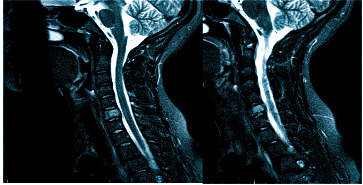

Если оно не дает необходимой картины по проблеме, то может быть назначена , а также: МРТ шейного отдела позвоночника

Важно! Если даже после подобной процедуры не станет ясна причина боли в голове, то потребуется дополнительная диагностика в виде МРТ, но уже позвоночника тела человека, а именно его шейного отдела.

Такие процедуры осуществляются не зависимо от того, есть ли в данный момент головные боли. Полноту информации для врача даст полный сбор анамнеза.

Врач определяет не только вид обследования, но и его объем. Иногда требуется дать оценку не только структурам мозга, но и воротниковой зоны: голова может кружиться и болеть при шейном остеохондрозе, грыже, воспалении нерва и пр.